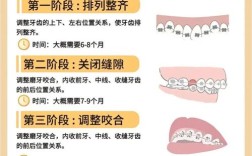

- 正畸辅助: 对于需要大量骨切除或牙齿位置不佳(如低位牙)的复杂病例,术前或术后进行正畸压低牙齿可以显著减少骨切除量,降低牙龈退缩风险,提高美学效果。